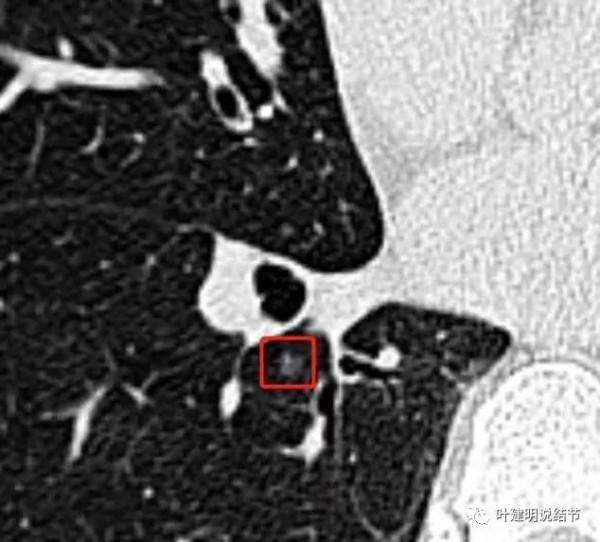

他是多發磨玻璃結節,但甚小,均不到1釐米的,而且密度低,位置也不好(不容易區域性楔形切除)。他透過網路問診諮詢我時,我認為風險低,可半年或一年隨訪複查,有進展時再考慮干預。但他也有問了國內非常有名的大伽,認為要考慮微浸潤性腺癌,建議手術治療。同樣,我的意見是:即使是微浸潤,甚至已經是浸潤性的貼壁型,繼續隨訪也是安全的呀!畢竟病灶小,又多發,要切的話,還無法只楔形切除。大家也都沒有碰到過浸潤性腺癌貼壁型的有轉移呀。我們如果跳出病理亞型,只按風險高低來判定是不是要干預,就會視野不一樣,也會讓更多肺結節患者減輕焦慮、輕裝工作,也能避過過於積極的外科干預,減少過度治療。